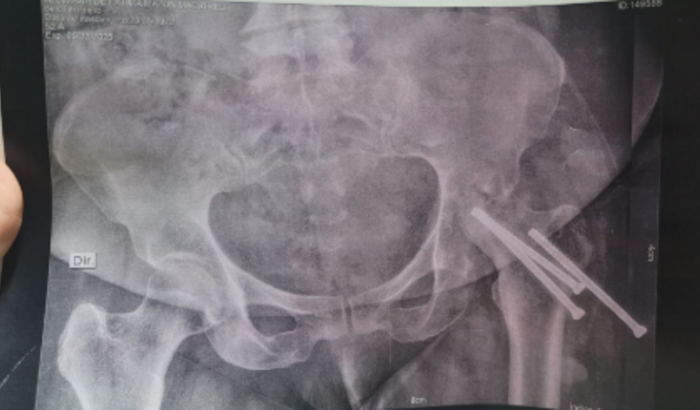

Voltou ao médico esse ano para um “retorno”, pois não aguenta de dor e está com o andar torto e voltou a usar bengala, pois não consegue andar sem apoio. Sugeriu uma cirurgia para colocar prótese, pois os parafusos estão soltando (conforme foto da radiografia), além de estar com o quadril extremamente torto e comprometido. Ela sente muita dor, e sempre toma remédios fortes para tentar alívio momentâneo. Como sabemos, o SUS demora muito tempo, mesmo sendo um caso urgente o médico deu pelo menos 1 ano de espera.